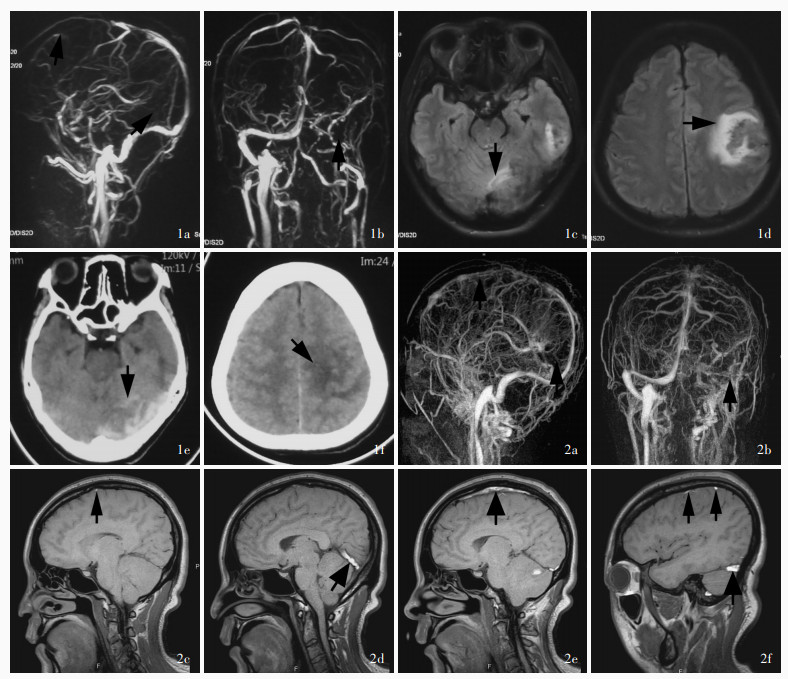

Hu SY , Zhang KY , Gu YQ , Li JK , Zhou C , Ji XM , Duan JG . Exploration of glucocorticoid combined with anticoagulation in acute/subacute severe cerebral venous thrombosis. Shou Du Yi Ke Da Xue Xue Bao, 2023, 44: 280- 288.

胡舒缘, 张开元, 谷亚钦, 李京凯, 周陈, 吉训明, 段建钢. 糖皮质激素联合抗凝在急性/亚急性重症颅内静脉血栓治疗中的探索. 首都医科大学学报, 2023, 44: 280- 288.

Hu S, Gu Y, Zhao T, Zhang K, Li J, Zhou C, Song H, Liu Z, Ji X, Duan J. Steroids combined with anticoagulant in acute/subacute severe cerebral venous thrombosis[J]. Chin Med J (Engl), 2025. [Epub ahead of print]